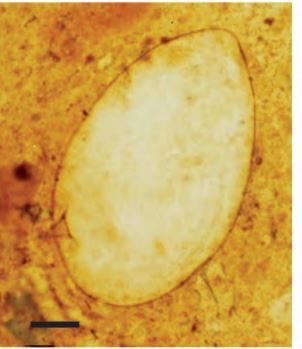

People infected with STH or intestinal schistosomes pass the eggs of the worms through their feces. Â In the Kato-Katz technique, feces are pressed through a mesh screen to remove large particles. A portion of the sieved sample is then transferred to the hole of a template on a slide. After filling the hole, the template is removed and the remaining sample is covered with a piece of cellophane soaked in glycerol. The glycerol clears the fecal material from around the eggs. The eggs are then counted and the number is calculated per gram of feces.

- Place the slide under a microscope and examine the whole area in a systematic zigzag pattern.

- Record the number and the type of each egg of each species on a recording form alongside the sample number.

- Finally, multiply the number of eggs**by the appropriate number (see inlet-information of the kato-set)**to give the number of eggs per gram (epg) – the standard measurement to assess the intensity of infection.